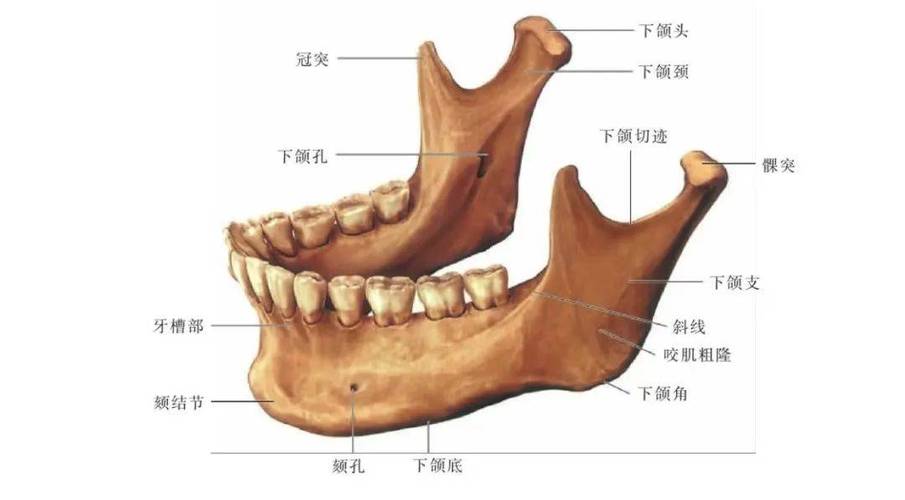

首先,讓我們來釐清一下,「智齒位置」究竟指的是什麼。簡單來說,智齒,學名為第三大臼齒,位於我們口腔的最裡面,也就是上下顎骨的最後方。一般人有四顆智齒,左右各兩顆,分布在上顎和下顎。然而,許多人的智齒並非都能順利萌出,它們可能因為空間不足、骨骼阻擋、鄰近牙齒的推擠,或是牙齦包覆等種種原因,而停留在骨頭裡,這就是我們常聽到的「埋伏智齒」。

這是診斷智齒位置最直接、最有效的方法。一般的全口X光片(Panoramic X-ray),或是更精確的電腦斷層掃描(CBCT),能清楚地呈現智齒在顎骨內的完整樣貌,包括它的傾斜角度、與鄰近牙齒和重要解剖結構(如神經管、鼻竇)的關係。

這是許多人對拔智齒最擔心的問題之一。下顎的智齒,尤其是靠近後方的智齒,其牙根位置確實可能與下顎神經管(Mandibular nerve canal)非常接近。下顎神經管裡面走行著負責下唇、下顎區域感覺的神經。

然而,現代牙科的X光技術,特別是CBCT,能夠非常精確地顯示智齒與神經管的距離和相對位置。牙醫師在手術前會仔細評估,並根據情況採取不同的手術策略來降低風險。

- 手術前仔細評估: 透過X光片,確認智齒與神經管的關係。